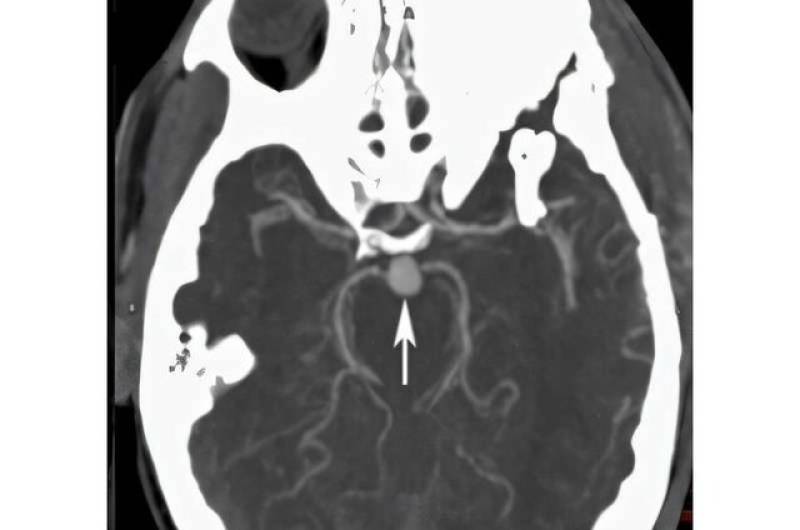

«آنوریسم مغزی» چیست؟/ علائم شایع و ۲ عامل خطر مهم آن

هر ساله نزدیک به نیم میلیون نفر در سراسر جهان بر اثر آنوریسم مغزی جان خود را از دست می‌دهند.